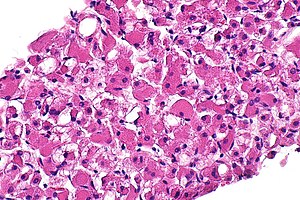

Rhabdomyoma. H&E stain. (WC) | |

| LM | spider cells (large polygonal cells (~10-20x RBC diameter), abundant cytoplasm with clearing) |

Features - cardiac:[3]

- Spider cells:

- Large polygonal cells (~10-20x RBC diameter):

- Abundant cytoplasm filled with glycogen.